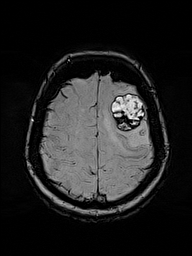

Case

De-identified demonstration

eigenMRI-CASE-014

Study

MRI Brain w/ Contrast

Date range

Baseline → Follow-up (Δ 14 days)

eigenMRI status

Monitoring

Focus

Structural boundary behavior

Outputs emphasize boundary behavior, structural continuity, and direction of change — without diagnostic framing.

eigenMRI is a deterministic reconstruction framework that applies eigenmode and Laplacian-based spectral analysis to standard MRI data. It enhances structural continuity, boundary definition, and subtle tissue transitions without modifying scanner hardware, pulse sequences, or contrast agents.